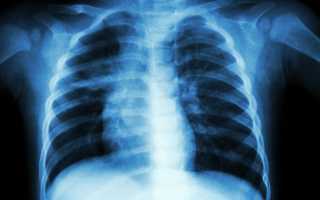

Выявить левостороннюю пневмонию у ребенка можно при помощи рентгенограммы. Данный метод для детей является самым оптимальным.